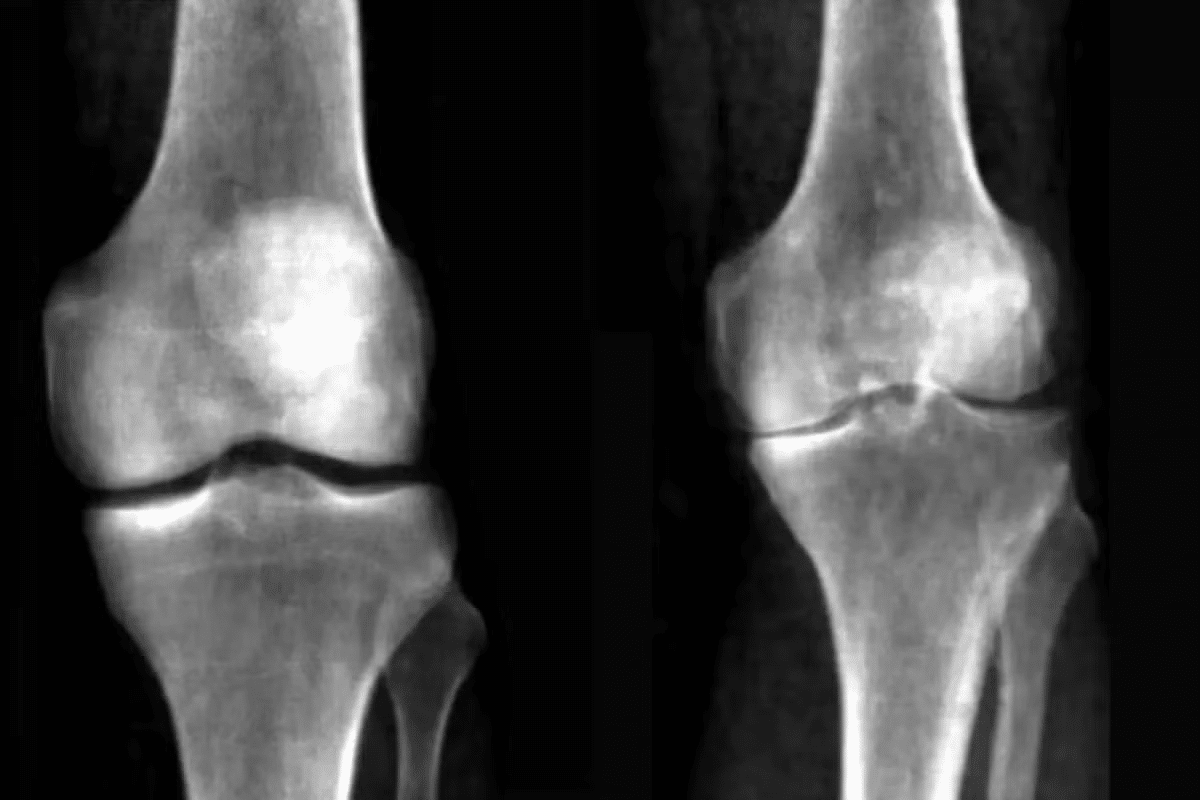

Imaging tests are very important for diagnosing CPPD. X-rays help us see if there’s calcium buildup in the cartilage. We might also use ultrasound or MRI to see more details about the joint and any crystals.

Chondrocalcinosis, joint damage |

CPPD can be told apart from osteoarthritis by looking at joint fluid and X-rays. Both can cause pain and stiffness. But, CPPD often shows more inflammation.